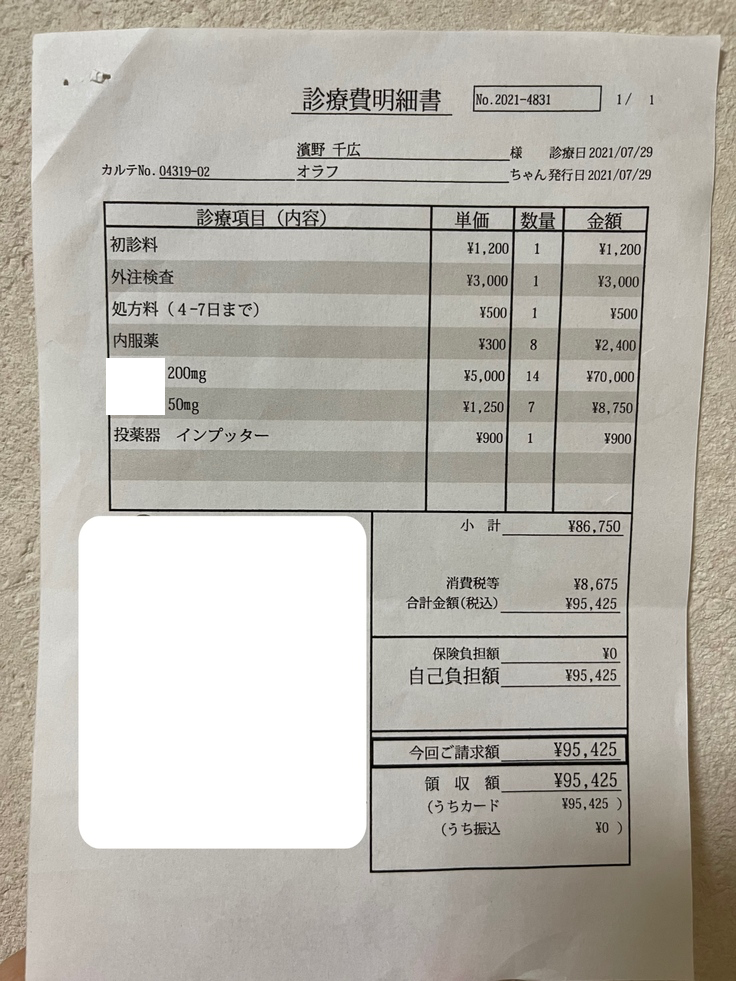

★薬代 8/3~8/26 12,375円(450mg)×24日

8/27~10/3 13,750円(500mg)×38日

10/4~10/25 15,125円(550mg)×22日

84日間の合計1,152,250円です。

★検査費等 85,382円

これまでのFIP治療費は1,237,632円です。

7月29日

ヒマワリのFIP治療をしたB病院で診ていただきたいと思い、オラフを連れて行きました。

A病院での血液検査を見てもらい、超音波検査を行いました。

熱はありませんでしたが、4cm程のしこりがあり腹水が少し溜まっていて、FIP混合タイプだろうと言われました。

オラフが新薬を投与する場合、1日約12,000~13,000円で84日間で約110万円かかります。

検査費と薬代です。

オラフの体重は3.0kgで1日450mg(計3錠)投与となります。

200mg(5,500円税込/錠)×2

100mg(2,750円税込/錠)

50mg(1,375円税込/錠)×1

3.4kgまでは1日¥12,375となります。